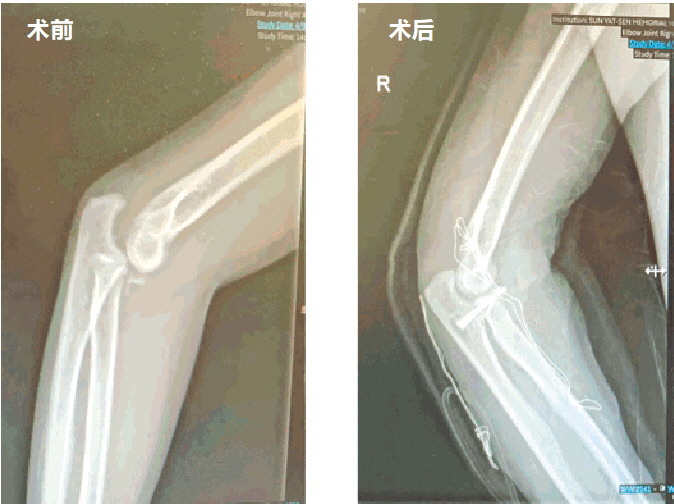

当他来到中山大学孙逸仙纪念医院运动医学科时,检查结果令人心惊:右肘关节处于固定性后脱位状态,同时合并两处关键骨折(桡骨小头和尺骨冠突骨折),肘关节解剖结构紊乱,关节僵硬性严重受损。接诊的陈仲副教授指出,这是从急性肘关节恐怖三联征拖成了更棘手的陈旧性损伤,并叠加了严重僵硬,治疗难度倍增。

面对如此复杂的情况,治疗团队决定采用分阶段策略:第一步行开放手术,重建骨性“地基”;第二步行关节镜微创手术,解锁关节活动。

术中,陈仲副教授团队首先对林先生肘关节进行广泛而有针对性的松解,使长期固定脱位的关节重新复位。随后,在恢复关节基本对位的前提下,对桡骨小头及尺骨骨折进行解剖复位与内固定,以重建骨性结构稳定。最后,对环韧带以及桡侧、尺侧副韧带进行修复,形成多层次的稳定结构重建,为术后功能恢复奠定了关键基础。

术后半年复查显示,林先生肘关节整体稳定性良好,但仍存在一定程度的关节僵硬及活动受限。团队充分评估后,在关节稳定性已得到保障的前提下,实施关节镜下精准拆除螺钉内固定及松解术,对关节内螺钉进行拆除,同时针对关节内瘢痕组织、关节囊挛缩及限制活动的结构进行系统松解。

术后随访近一年,林先生肘关节活动度完全恢复,重新开始进行搬运重物等较高负荷的体力活动。